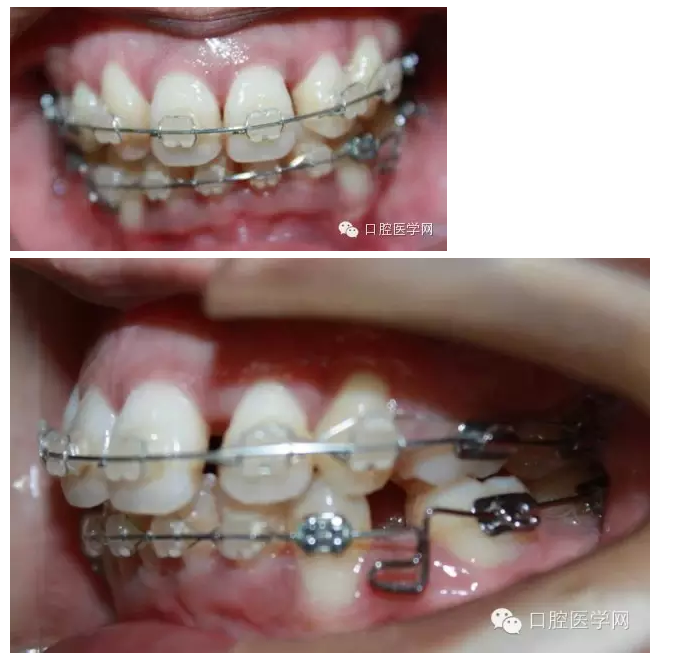

之后我換用0.018x0.025不銹鋼絲,在33,43遠(yuǎn)中彎制水平曲,階梯曲,結(jié)果3個月后,效果不明顯,而且牙齒變得有一些不整齊之后我再次用0.016x0.022niti絲,排了一下,在33,43的遠(yuǎn)中彎制后傾曲。

最后我用0.016x0.022不銹鋼絲,在33,43遠(yuǎn)中彎制水平曲,階梯曲和后傾曲,3個月后,深覆合明顯緩解。

這個病例花了9個月時間,才明顯壓低下前牙,打開咬合。這期間有很多值得我們思考的地方。

二、由于患者是重度深覆合,極為嚴(yán)重的深Spee曲線,所以我們使用niti絲加力,必然導(dǎo)致力量分散。其實排齊后,患者錯合畸形的關(guān)鍵在于尖牙和磨牙之間弓絲的轉(zhuǎn)折

但如果我們換成不銹鋼方絲,彎制曲之后,第一、第二磨牙之間為剛性關(guān)系,下前牙之間也是剛性關(guān)系,都不容易變形,只有尖牙和磨牙之間是曲,保持輕柔而持續(xù)的力量,有利于矯治力量效果的釋放。